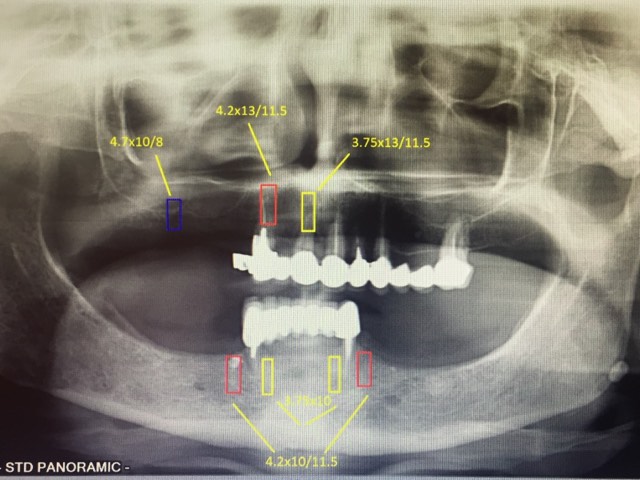

Мастер-класс начался с обсуждения предстоящей операции и исследования компьютерной томографии, после чего участники смогли присутствовать на операции или следить за ней из учебного центра.